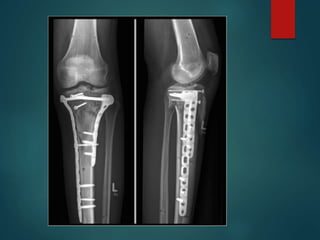

Tibial Plateau Fractures

 Treatment

 Definitive ORIF for patients with

varus/valgus instability, >5mm

articular stepoff

 Non-operative in non-displaced

stable fractures or patients with poor

surgical risks